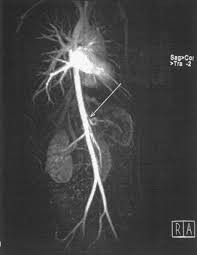

Ct Of The Abdomen The Origin Of The Celiac Artery Arrow Shows A Download Scientific Diagram